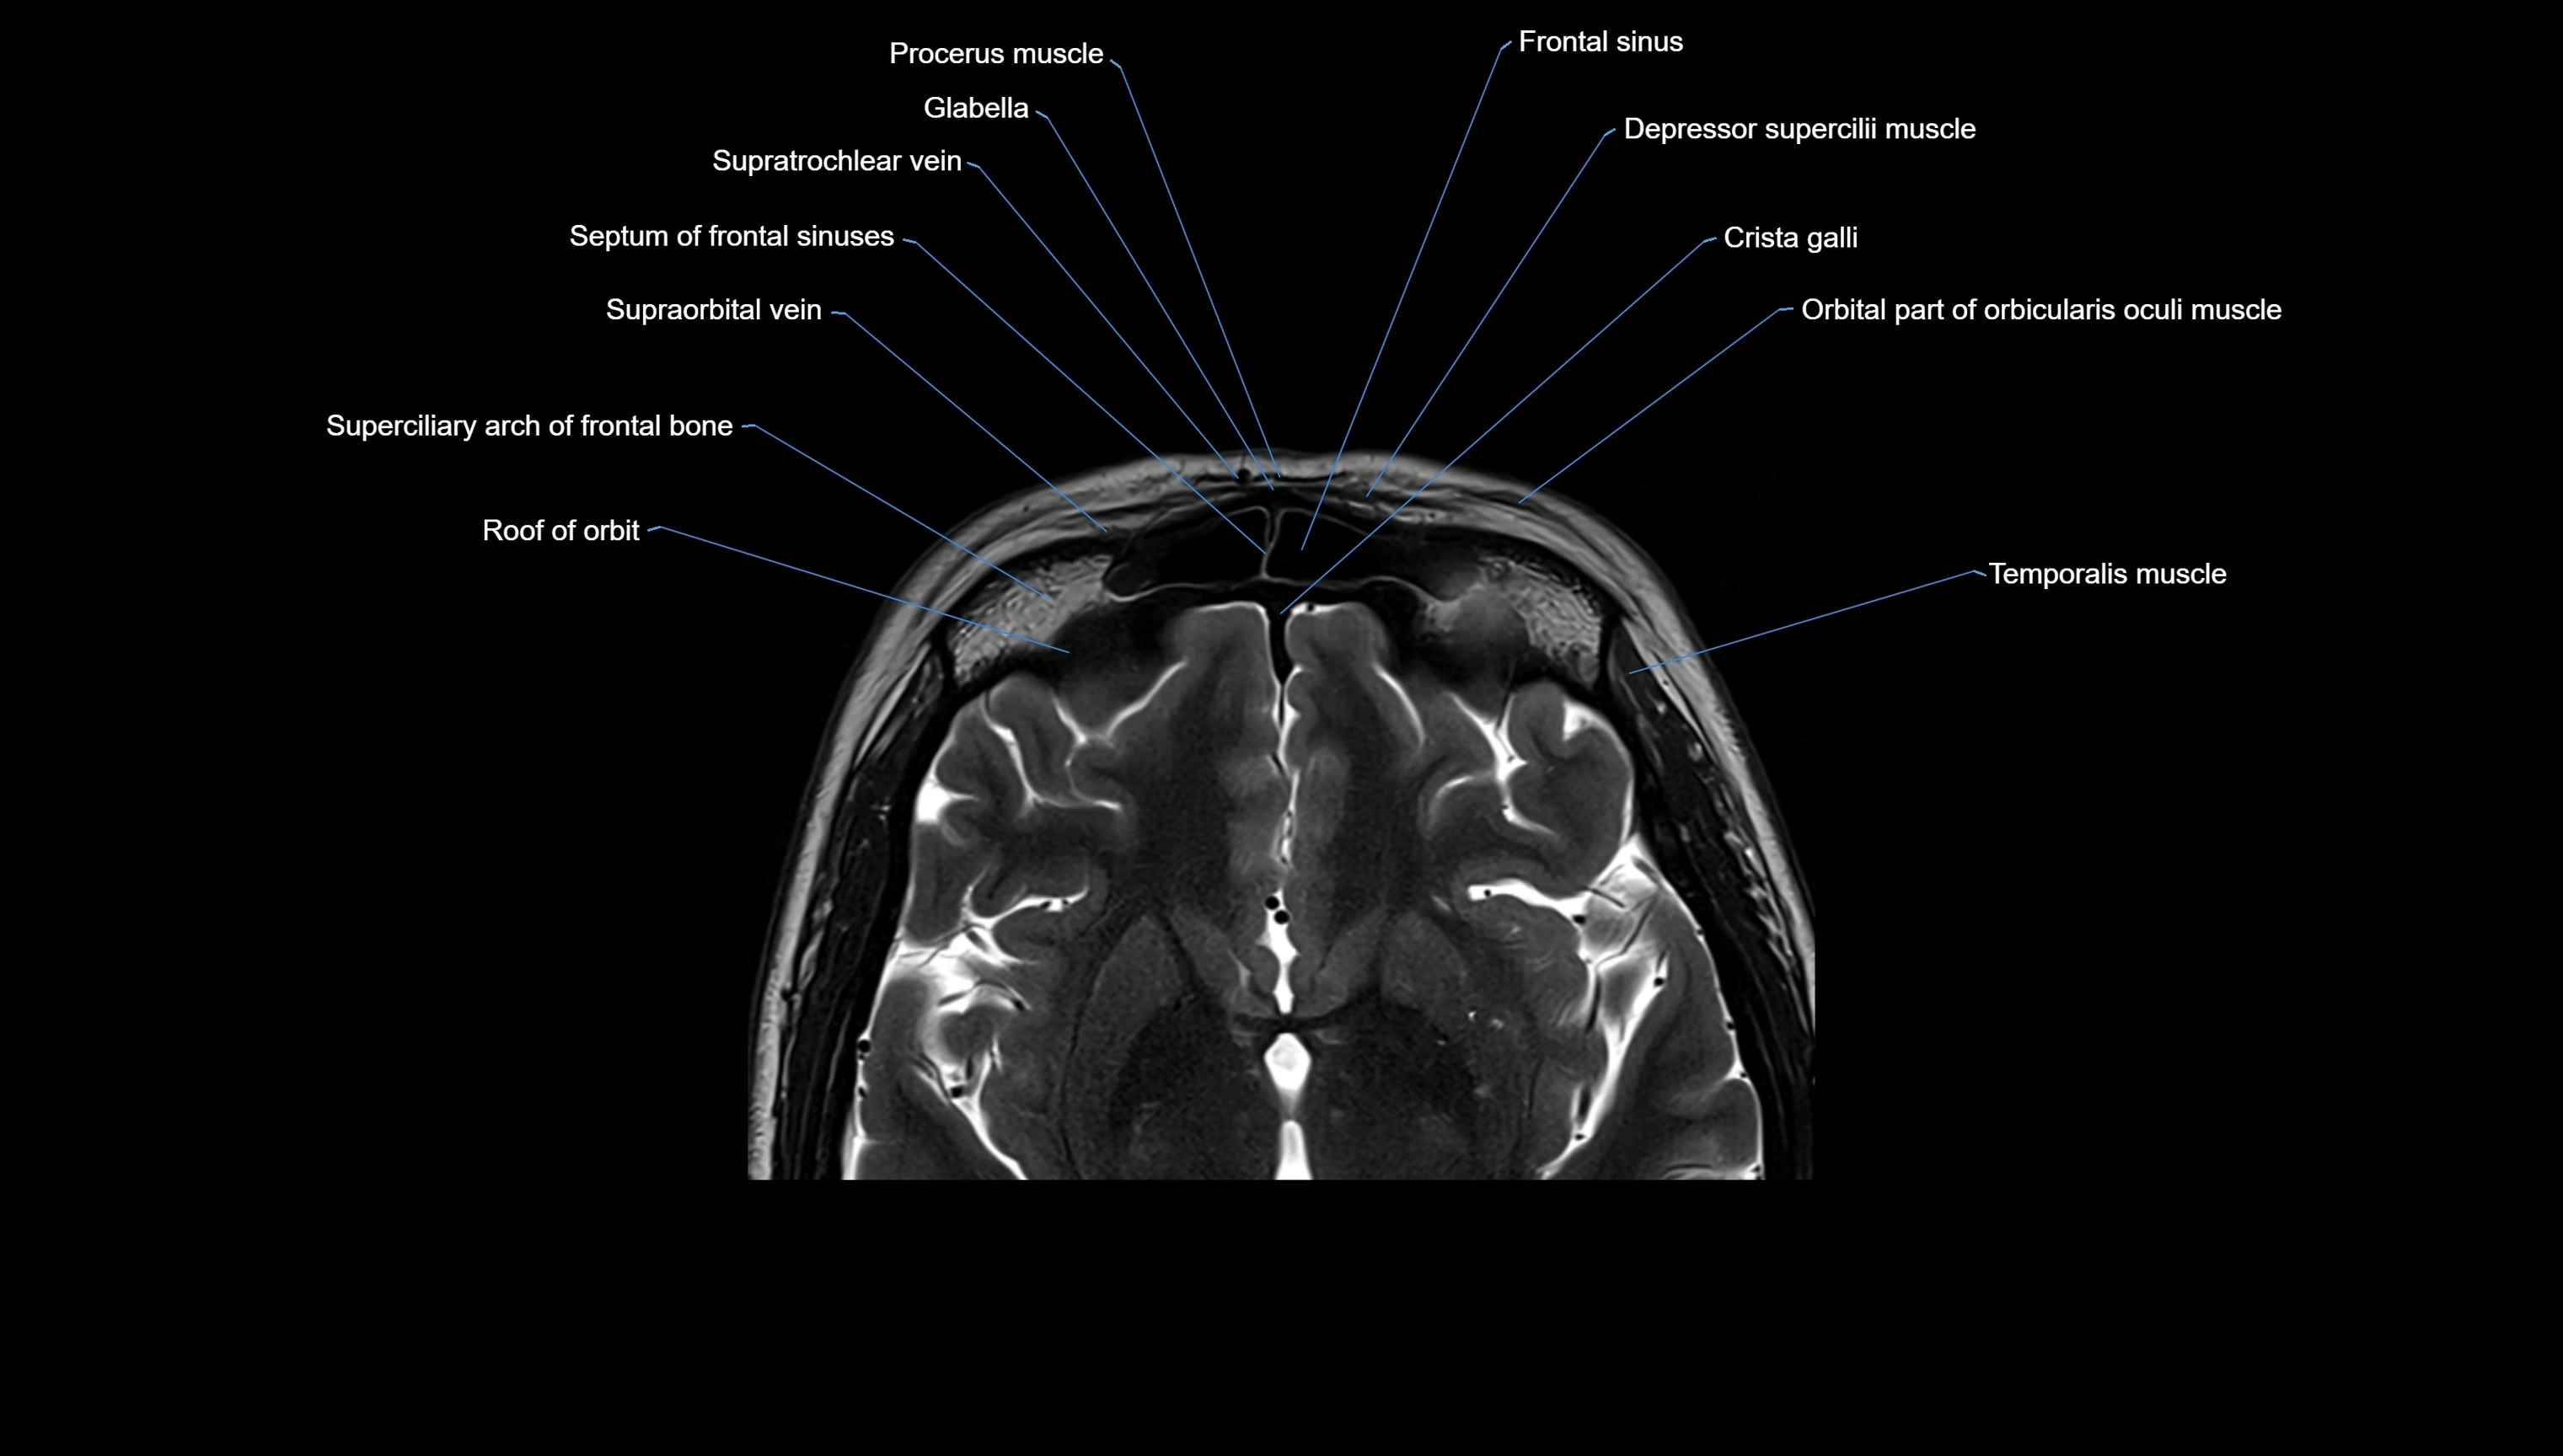

MRI images